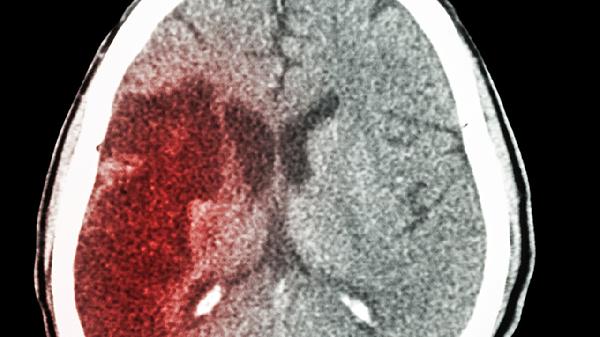

开颅后脑积水通常可以治好,治疗方法主要有脑室腹腔分流术、内镜下第三脑室造瘘术、药物治疗、康复训练、定期随访等。脑积水可能与颅内出血、感染、肿瘤等因素有关,通常表现为头痛、呕吐、视物模糊等症状。建议及时就医,在医生指导下选择合适的治疗方案。